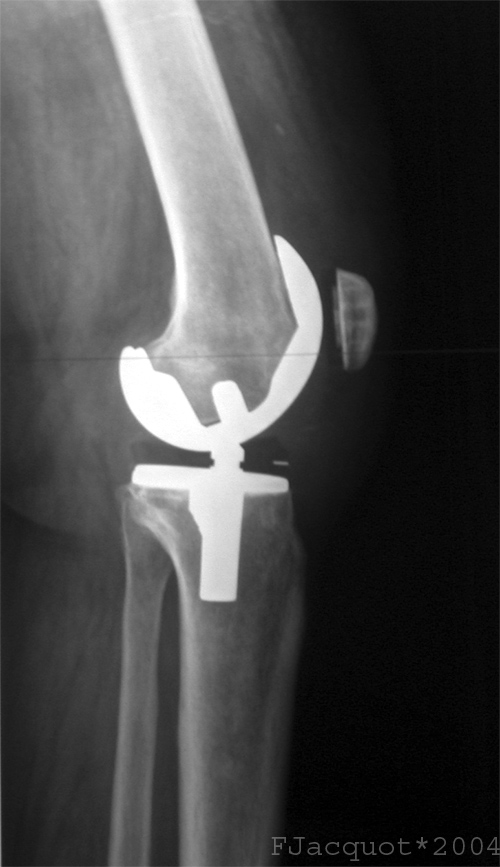

Lateral view of a total knee prosthesis taken from a radiograph . Source: Public DomainKnee Replacement wound close by staples. Source: Public Domain